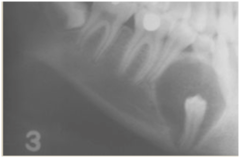

sialolith

-obstruction in the gland hard nodule in soft tissue at a salivary gland -calcification of material -can be seen radiographically